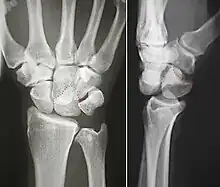

The lunate bone is the most frequently dislocated carpal bone.

Dislocated lunate